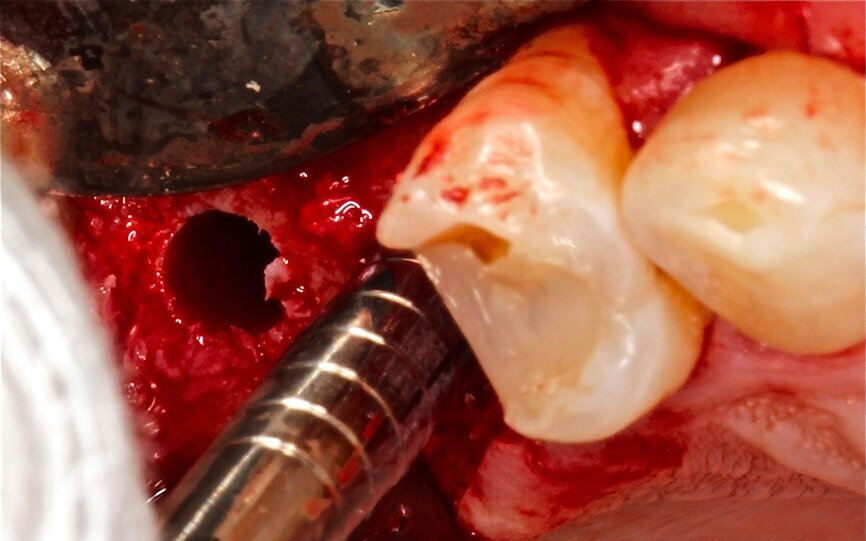

Fig. 10 Figura 10

1. Inserción del implante, con una estabilidad primaria correcta y posición prostodóntica ideal.

2. Realización de perforaciones en el lecho con fresa redonda para aumentar la disponibilidad de células osteogénicas y acelerar la revascularización y mejorar la unión injerto huésped.